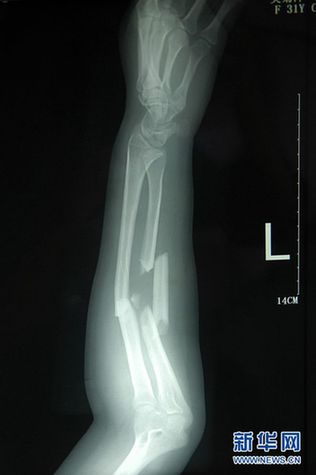

這是7月3日拍攝的吳菊萍受傷左臂的X光片,醫(yī)生診斷為手臂左尺橈骨多段粉碎性骨折。 新華社記者 黃宗治 攝